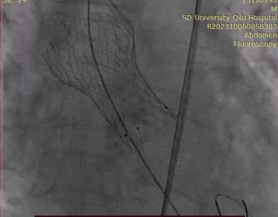

近日,安贵鹏副教授团队还受邀在拉丁美洲最大的心血管病学术会议——2023年拉丁美洲介入心脏病学会年会(SOLACI)上分享了二叶式主动脉瓣的TAVR治疗经验。董梅副教授代表团队介绍了中国二叶式主动脉瓣的病变特点,通过一例无钙化大瓣环横位心TAVR,生动展示了如何为BAV患者行介入治疗,在国际会议上分享了中国术者在二叶式主动脉瓣TAVR治疗的经验和心得,精彩汇报受到了与会各专家的一致好评。